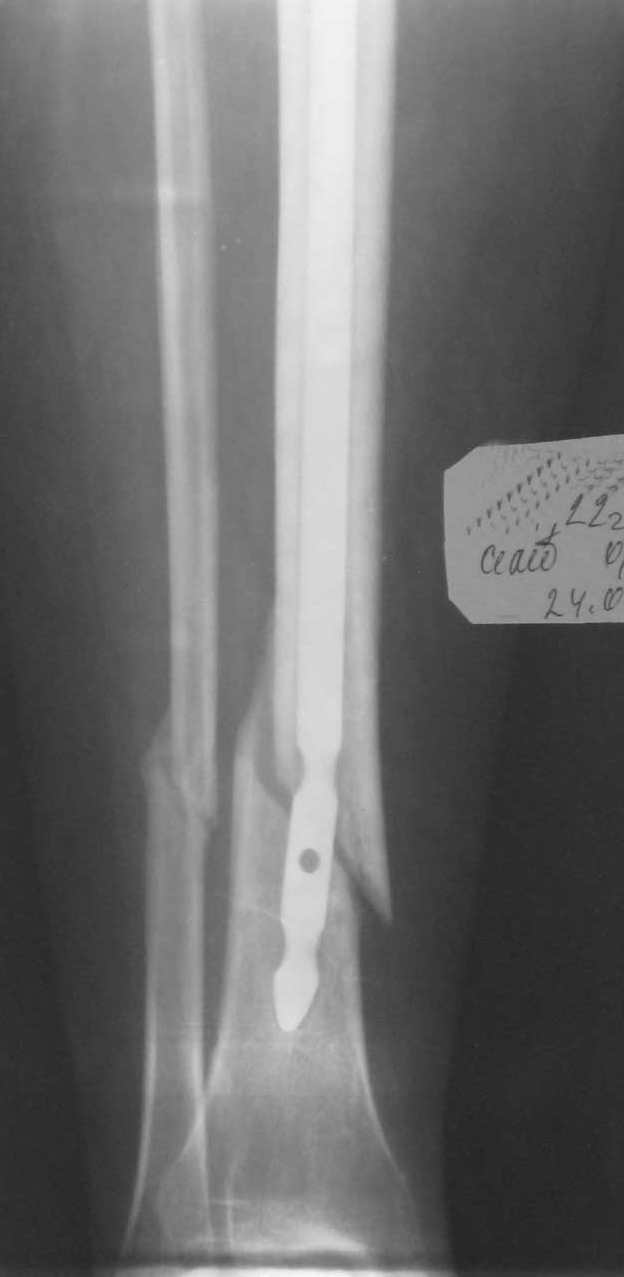

Здравствуйте уважаемые доктора! 18.01.2009 каталась на коньках, сломала ногу. У меня закрытый перелом костей н/3 правой голени со смещением обоих костей. 30.01.09 г. сделали операцию, остеосинтез штырем и 4 винтами, до этого находилась на скелетном вытяжение за пяточную кость. После снятия швов, надели лангет без закрытия пальцев до колена. 13.03.09 г. под м/а выполнено удаление 2 винтов, разрешена дозированная нагрузка (наступаю на костылях в лангете, функция суставов практически без ограничений). До операции врачи говорили, что в ранние сроки смогу приступить к полноценной жизни, прошло больше 3 месяцев со дня операции но возвращение к полноценной жизни так и не произошло. Последний снимок сделала 24.04.09 г., посмотрев снимки врач сказал, что консолидация перелома слабая и рекомендовал еще 1 месяц до следующего снимка продолжать ходить на костылях с дозированной нагрузкой.Меня беспокоят снимки, кости сопоставлены не совсем ровно (это только мое мнение, не знаю как должно быть). Почему так долго не срастается перелом, сроки срастания с таким диагнозом? Когда начинать бить тревогу? Что можно сделать, что бы ускорить процесс заживления?- Мне 22 года- Не курю, ни каких заболеваний нету- Принимаю кальций Д3 Никомед, МУМИЕ, хорошее питаниеБуду рада получить от Вас любую полезную информацию.Заранее благодарю всех тех, кто со вниманием отнесется к моей проблеме.

По снимкам - несостоятельный остеосинтез. Нижний отломок большеберцовой кости стержень не удерживает, тем более и винтов в нем нет. Есть неустраненное значительное смещение. Возможно, стержень уже сломан (есть его деформация).

Остеосинтез надо переделать, стержень взять потолще и ввести поглубже, устранив попутно все смещения, и запереть в нижнем отломке 3 винтами. Кальций Д3 не нужен, мумие вообще нонсенс (XXI век на дворе!).